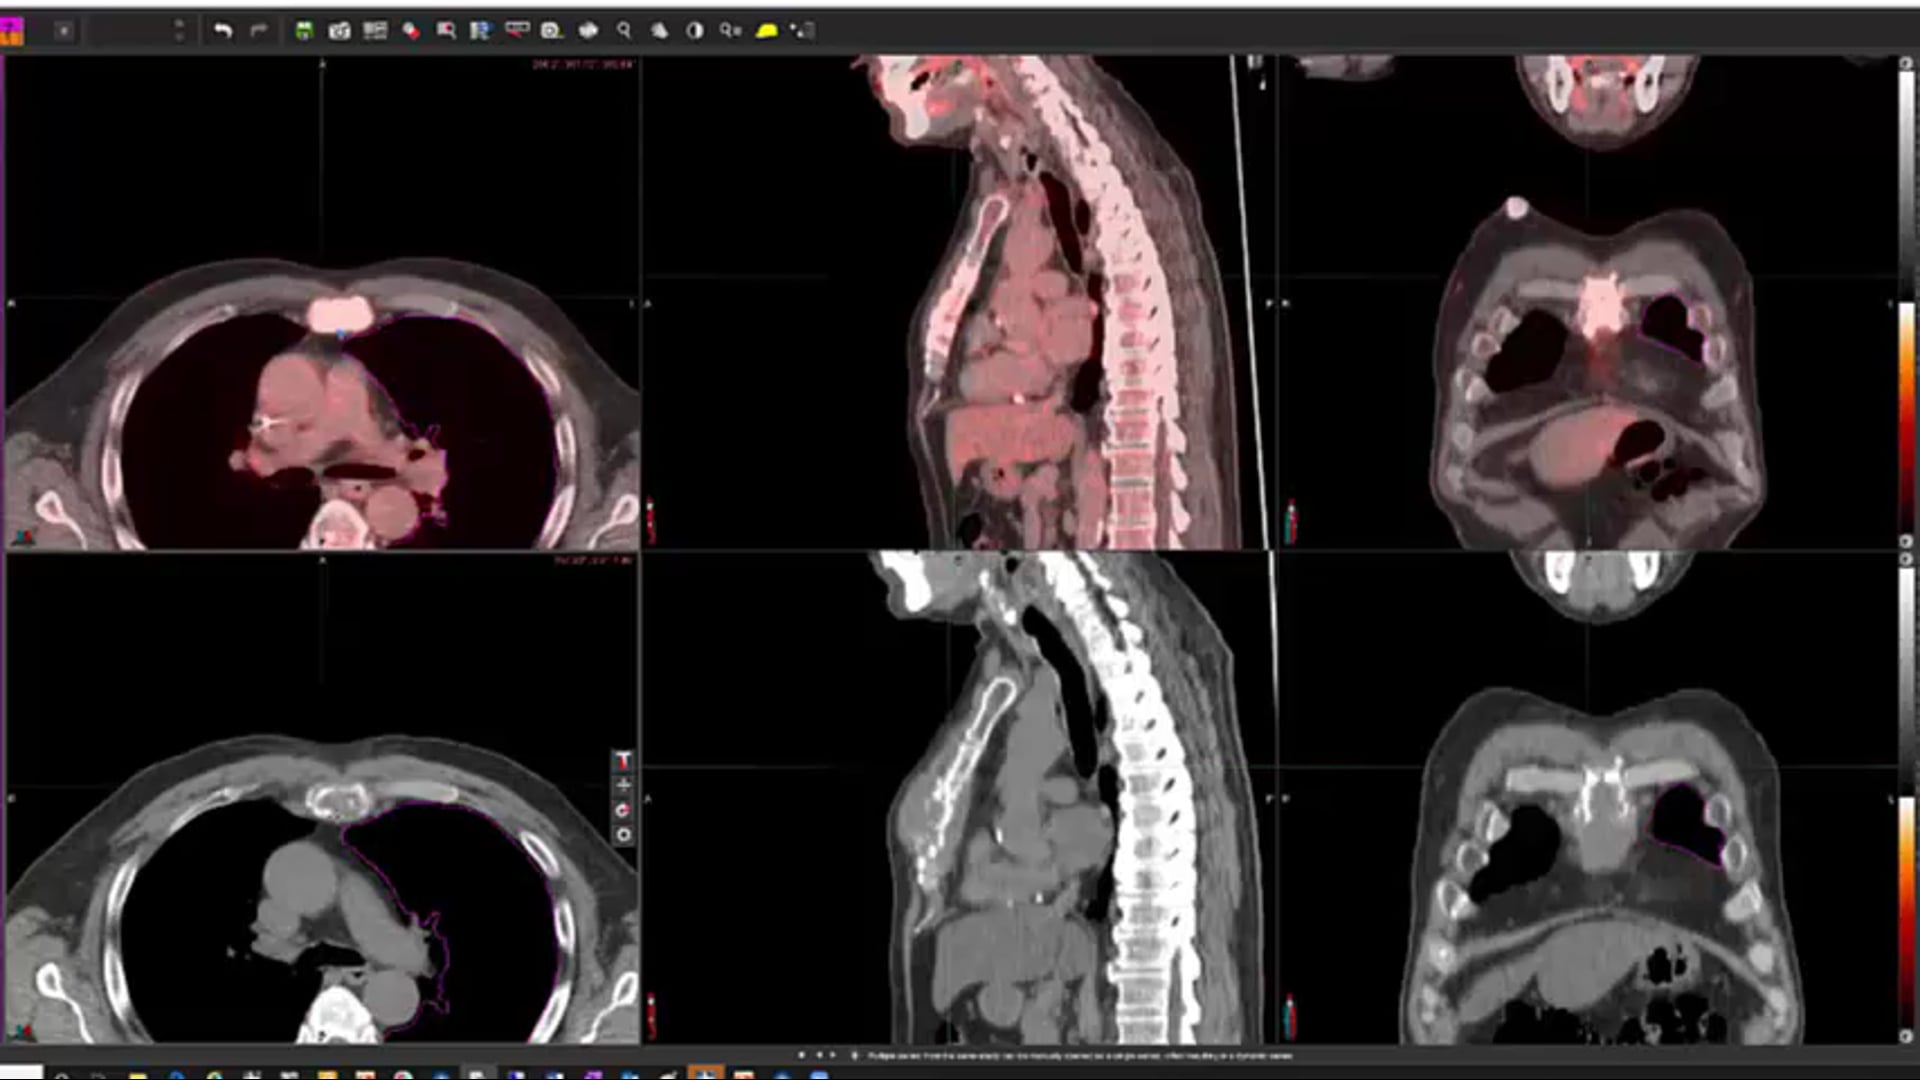

Follicular lymphoma, R-CHOP Chemotherapy, DLBCL, nodular lymphoma, post treatment scans, testicular lymphoma, photons vs. electrons, target volumes, dose, side effects, paranasal lymphoma, elderly, multiple myeloma, bone mets,

nodular sclerosis, Hodgkin's lymphoma, supraclavicular lymph nodes, MALT lymphoma, CLL,